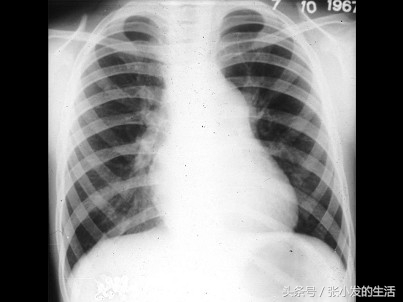

82[单选题]男孩,8岁。体检时发现胸骨左缘第2肋间有粗糙喷射性全收缩期杂音,向颈部传导,肺动脉瓣区第2音减弱。经右心导管检查,证实为中度肺动脉瓣狭窄。进行X线检查,如图所示,下列哪一项不是特点 ( )

A.偶尔右心房增大

B.右心室有不同程度增大

C.肺动脉段多平直

D.肺动脉总干膨出

E.肺血减少,肺野清晰

正确答案:C